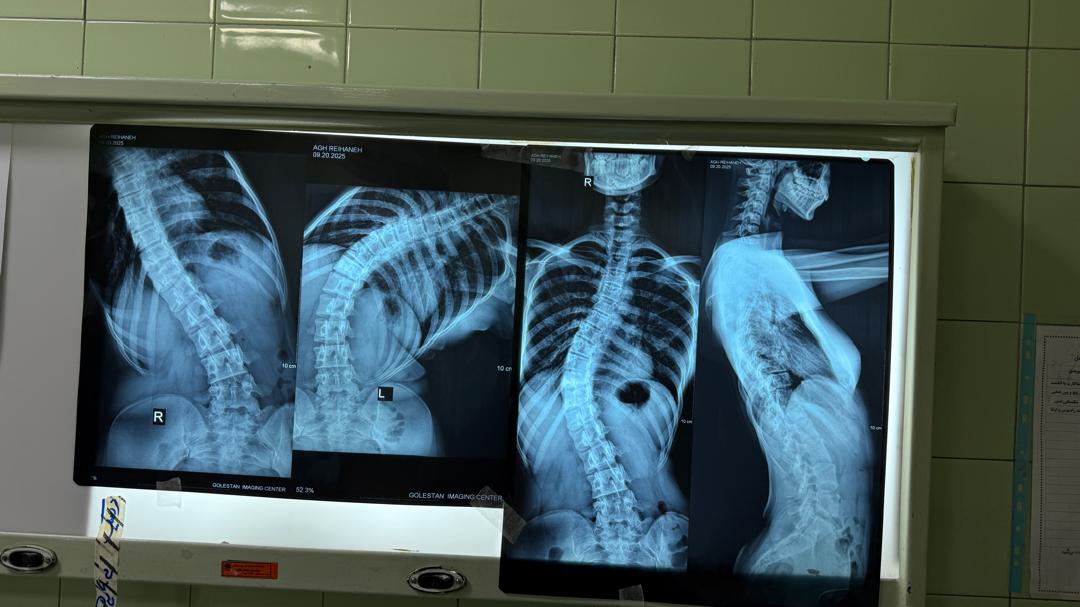

عمل جراحی اصلاح کجی ستون فقرات یا اسکولیوز در خانم جوانی که به دلیل سل استخوانی در کشور افغانستان تحت جراحی قرار گرفته بودند و عمل ایشان موفق نبود در ضمن قسمت بزرگی از پوست و ماهیچه های ناحیه پهلوی بیمار از بین رفته بود که توسط اینجانب تخلیه توده سل و اصلاح کجی یا اسکولیوز ستون فقرات انجام شد و توسط همکاران جراحی پلاستیک، نقص پوست و ماهیچه از طریق روتیشن فلپ ترمیم گردید